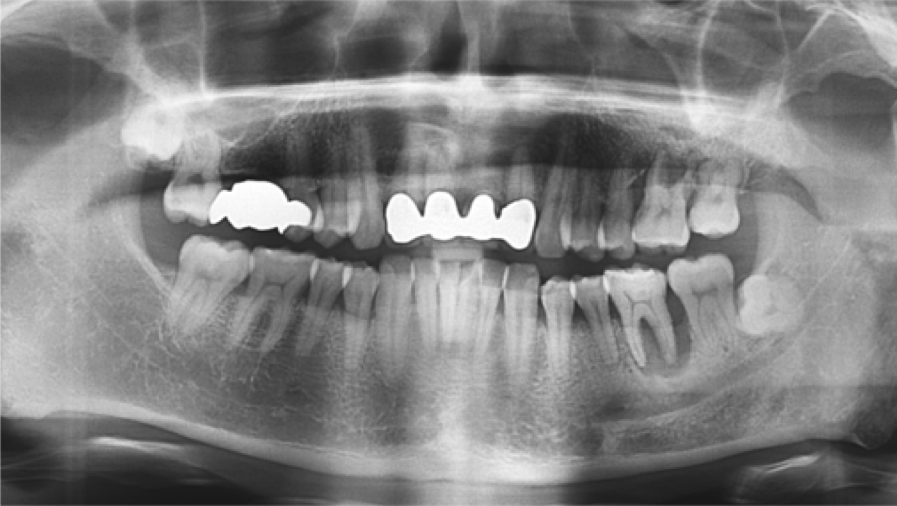

“Immediate loading of single AnyRidge implants

is a highly successful treatment modality. ”

Clinical case: Immediate post-extraction insertion of implant & immediate loading

- Courtesy of Prof. Giuseppe Luongo, Italy -

AnyRidge, immediate loading, single implant, multicenter study, maxillary anterior, Prof. Giuseppe Luongo, single replacement

AnyRidge implant system

Immediate functional loading of single implants: a multicenter study with 4 years of follow-up

/J Dent Res Dent Clin Dent Prospect 2018; 12(1):26-37 | doi: 10.15171/joddd.2018.005

https://www.ncbi.nlm.nih.gov/pubmed/29732018